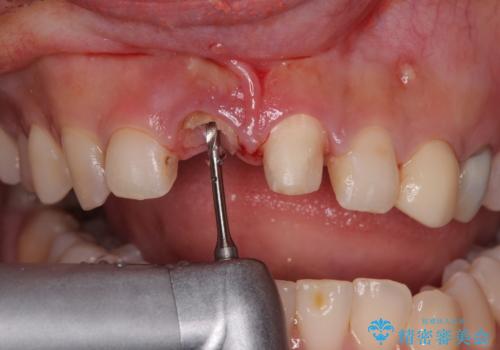

▶右上中切歯

抜歯後、即時インプラント埋入

審美性を考慮し、仮歯を即日装着